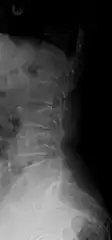

Example of vertebral compression fracture.

A compression fracture is a collapse of a vertebra. It may be due to trauma or due to a weakening of the vertebra (compare with burst fracture). This weakening is seen in patients with osteoporosis or osteogenesis imperfecta, lytic lesions from metastatic or primary tumors,[1] or infection.[2] In healthy patients, it is most often seen in individuals suffering extreme vertical shocks, such as ejecting from an ejection seat. Seen in lateral views in plain x-ray films, compression fractures of the spine characteristically appear as wedge deformities, with greater loss of height anteriorly than posteriorly and intact pedicles in the anteroposterior view.[3]

A potential complication of a vertebral compression fracture is avascular necrosis of the vertebral body, which is called Kümmel's disease, and may appear with the intravertebral vacuum cleft sign (at white arrow in image).[4]

Compression fractures are usually diagnosed on spinal radiographs, where a wedge-shaped vertebra may be visible or there may be loss of height of the vertebra. In addition, bone density measurement may be performed to evaluate for osteoporosis. When a tumor is suspected as the underlying cause, or the fracture was caused by severe trauma, CT or MRI scans may be performed.